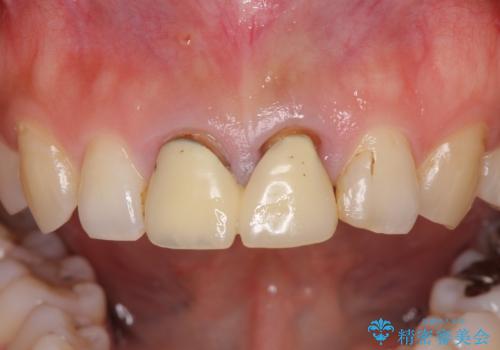

- 前歯のクラウンが着色により不自然な色となっていることを気にして来院された患者様です。

クラウンと歯の縁も合っておらず、汚れが溜まりやすい環境であったため、前歯2歯のクラウンをオールセラミッククラウンにて再補綴することとしました。

また、下顎前歯の叢生も気になっているとのことで、上顎の治療と並行して部分矯正を行うこととしました。